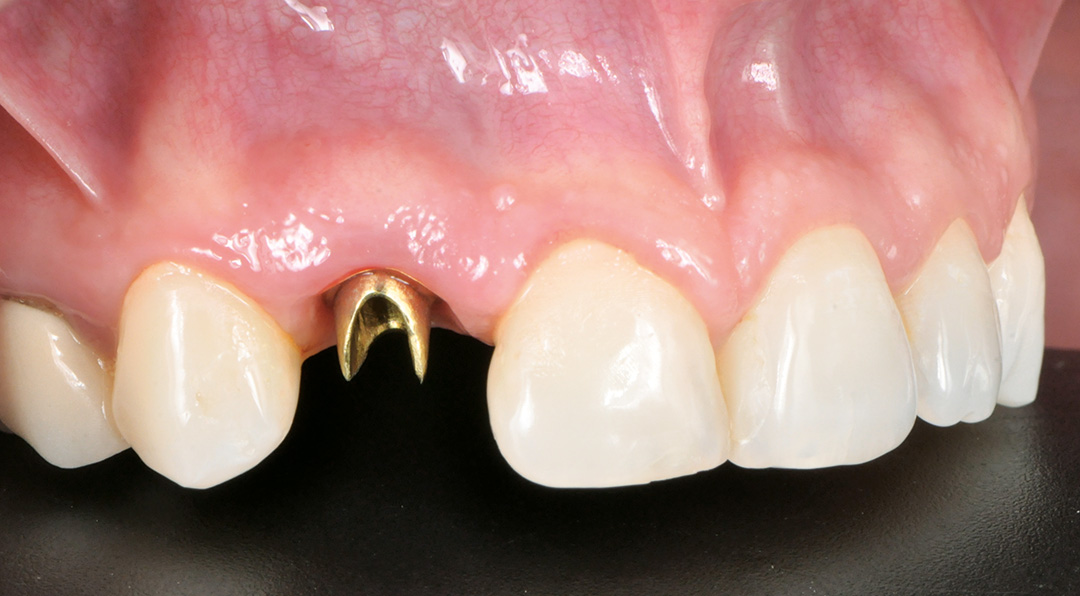

A patient presented with a horizontal fracture of the upper left lateral incisor (tooth 1.2), with no clinical signs of suppuration or bleeding. The periodontal phenotype was thin, and the buccal bone wall was minimally thick, increasing the risk of soft tissue recession following extraction. A minimally invasive and digitally planned treatment was chosen to preserve tissue architecture and ensure a predictable aesthetic result.

Surgery and initial outcomes

A minimally invasive extraction was performed using the Benex® system to preserve the thin buccal bone. A 3.3 x 11 mm CONELOG PROGRESSIVE-LINE implant was placed using a fully guided protocol. Despite the narrow implant diameter, a torque of 20 Ncm was achieved, facilitated by good palatal bone availability, under-preparation of the osteotomy and the macro design of the implant. The peri-implant gap was grafted with MinerOss X, chosen for its slow resorption profile and volume-stabilising characteristics. A connective tissue graft was harvested from the tuberosity by performing a distal wedge in the region of tooth 1.8. The graft was secured in a buccal pouch using a horizontal mattress suture with 6-0 polypropylene to support the emergence profile and soft tissue volume. A customised healing abutment was placed to seal the socket and guide soft tissue healing. A provisional resin-bonded restoration was applied out of occlusion.